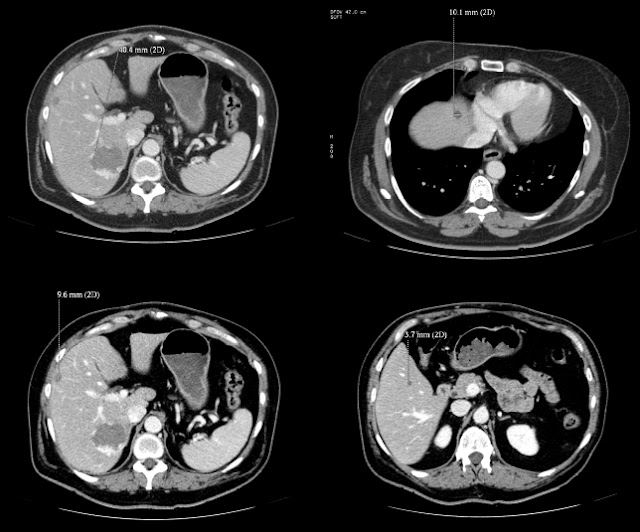

Hace

dos noches me avisaron para trasladar al servicio de cardiologia de

nuestro hospital de referencia a una paciente de 90 años de edad,

Hipertensa y diabética insulindependiente porque había tenido un sincope. Portaba un marcapasos desde el 2009 por una disfunción sinusal sintomática

sin ritmo auricular propio y que había tenido un recambio del

generador el año pasado. Estaba anticoagulada por una fibrilación

auricular permanente y a tratamiento con

Amiodarona. Nuestra

paciente, tenía además muchos mas antecedentes médicos que no

vienen al caso y que no cuento para no liar mas las cosas y llegó a

nuestro servicio de urgencias consciente, pálida, taquicardica,

taquipneica, hipotensa y con una bradicardia extrema de unos 20 lpm.

A

día de hoy esta paciente

tiene un electrodo implantado por vía subclavia izquierda al VD y ha

salido de una parada cardíaca durante el implante.